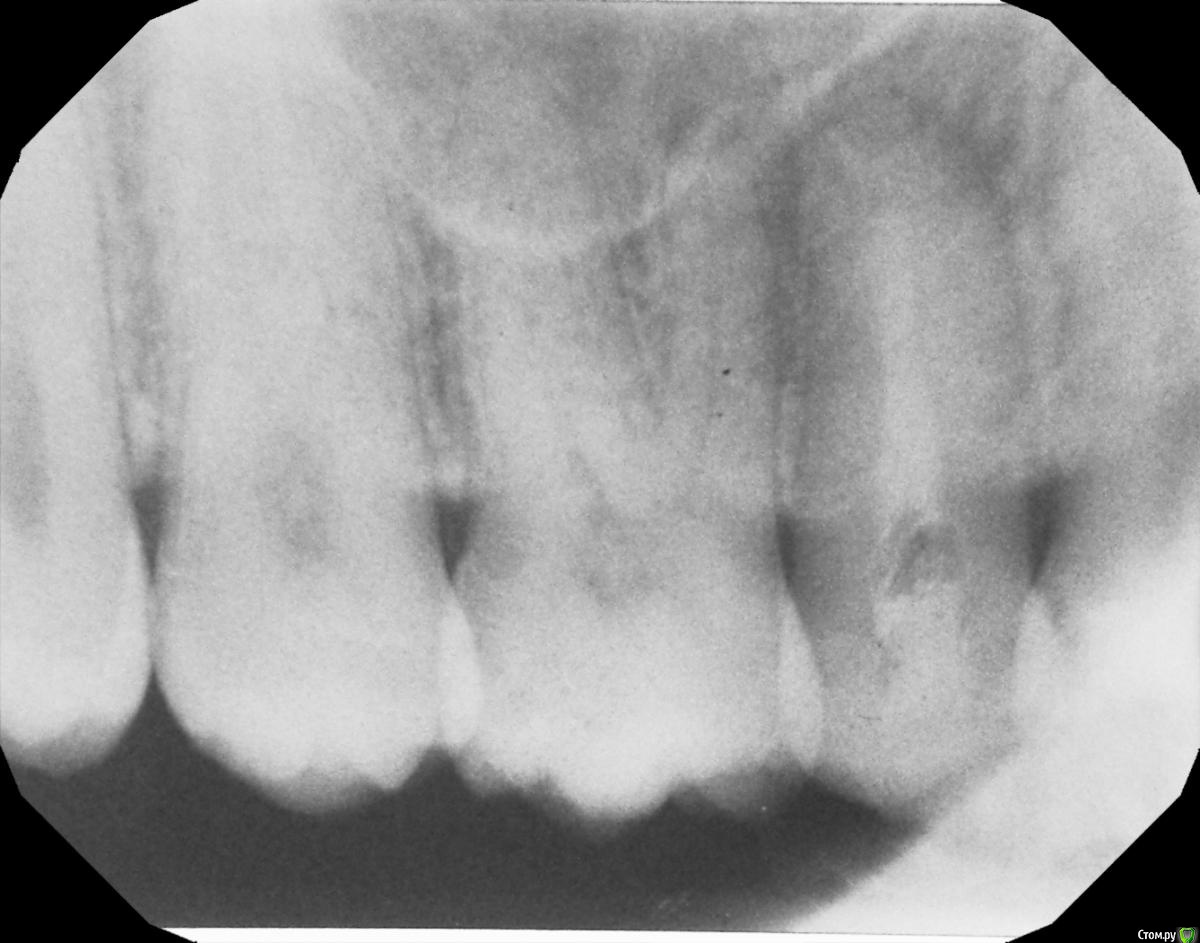

hichi Опубликовано 19 сентября, 2015 Поделиться Опубликовано 19 сентября, 2015 Добрый день. 6 месяцев назад проведено эндодонтическое лечение зуба. После этого через 1.5 - 2 недели острая боль от горячего. Подозревали дополнительный канал, зуб еще раз вскрыли, но ничего не обнаружили, еще раз обработали тот же самый канал и поставили кальций на 2 недели. На сегодняшний день реакции на горячее нет, но острая боль при чистке нитью между 1.4 и 1.5. когда вводишь и выводишь нить через контактный пункт. Как только пройдешь контактный пункт боль сразу же проходит. Десна не болит. Карманов нет. Кариеса тоже нет. Пару месяцев назад частично заменили пломбы в районе этого контактного пункта, но ничего не изменилось. Прилагаю снимок через 6 мес. Оцените, пожалуйста, все ли в порядке? Спасибо. Ссылка на комментарий

hichi Опубликовано 25 сентября, 2015 Автор Поделиться Опубликовано 25 сентября, 2015 (изменено) покажите все снимки начиная с первого Гарриевич сказал(а) 22 Сен 2015 - 00:35: покажите все снимки начиная с первого + 1 пожалуйста первичное эндо когда заболел от горячего искали доп. анатомию кальций с ложным ходом есть только один снимок, который в самом первом сообщенииесть еще один через 3 мес после лечения но он не совсем удачно сделан, думаю ничем вам не поможет Изменено 25 сентября, 2015 пользователем hichi Ссылка на комментарий